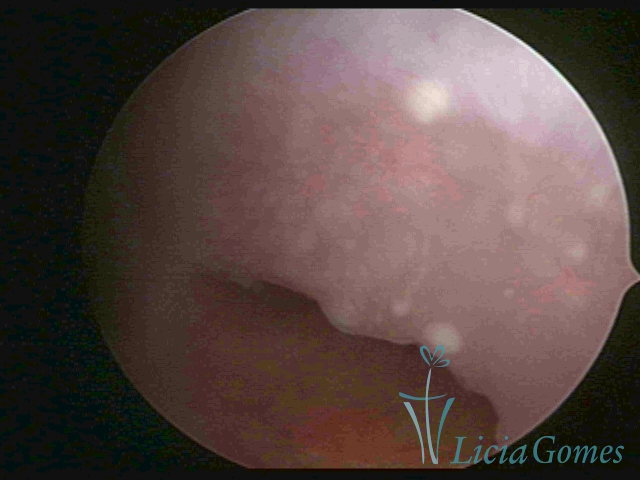

Terceira porção ou porção superior

Apresenta a mucosa com a superfície lisa e pouco vascularizada até a altura do orifício interno